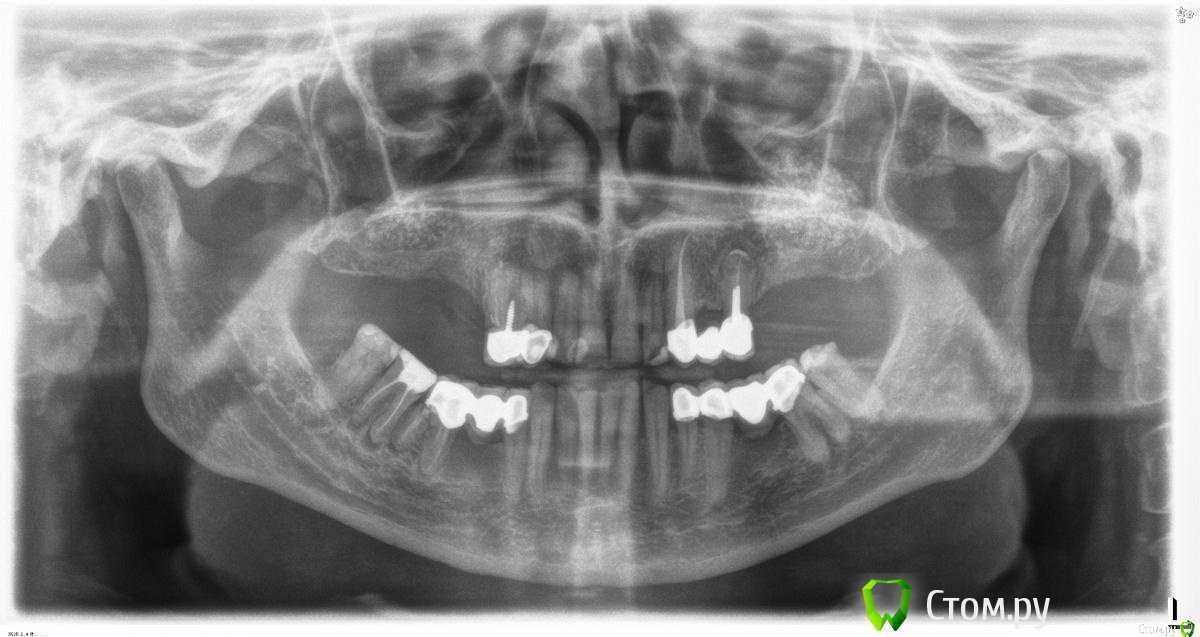

red_butler Опубликовано 16 октября, 2015 Автор Поделиться Опубликовано 16 октября, 2015 Сегодня продолжил, качество кости совсем не понравилось, но окно закрылось, пришлось ушить винты.Теперь думаю отложить 2 этап на 5-6 месяцев.http://s017.radikal.ru/i413/1510/09/0c8ba121c636.jpg Ссылка на комментарий

Фарид Расулыч Опубликовано 16 октября, 2015 Поделиться Опубликовано 16 октября, 2015 (изменено) А я не люблю гиперсинусы. так как считаю в этом нет смысла. ставить в пазуху винт 17 мм? А нафига он там такой длинный? А прорастет ли графт которыйпод куполом?? Я думаю нет.Поэтому и не извожу материал в таких колличесвах.)на 1 см или на 1.5 вполне хватит)Понятно что апикальный упор это хорошо, но 1 см над имплантом это борщ)Тем более что на 25м импланте его вообще нет. Да и Дентиум тут будет стоять и так хорошо. ИМХО, опять же.) Изменено 16 октября, 2015 пользователем Фарид Расулыч Ссылка на комментарий

red_butler Опубликовано 16 октября, 2015 Автор Поделиться Опубликовано 16 октября, 2015 Рыхло?Торк какой получили?Не то слово, торк около 15 Ссылка на комментарий